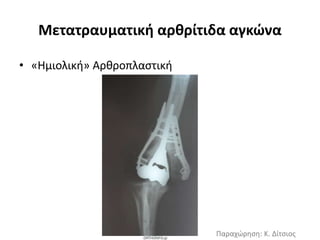

Μετατραυματική αρθρίτιδα αγκώνα

Δεύτερη σε συχνότητα- συνήθως αφορά

νέα δραστήρια άτομα

▪Αρθροσκοπική ή ανοικτή εκτομή

οστεοφύτων, χονδροπλαστική,

αφαίρεση ελεύθερων οστεοχόνδρινων

σωμάτων

▪Αρθροπλαστική παρεμβολής με

αυτομόσχευμα ή αλλομόσχευμα

▪“Ημιολική” αρθροπλαστική -μικρές

σειρές

• «Ημιολική» Αρθροπλαστική

Παραχώρηση: Κ. Δίτσιος